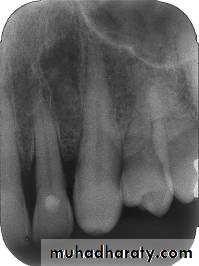

Maxillary incisor region

Maxillary canine region

Maxillary premolar region

Maxillary molar region